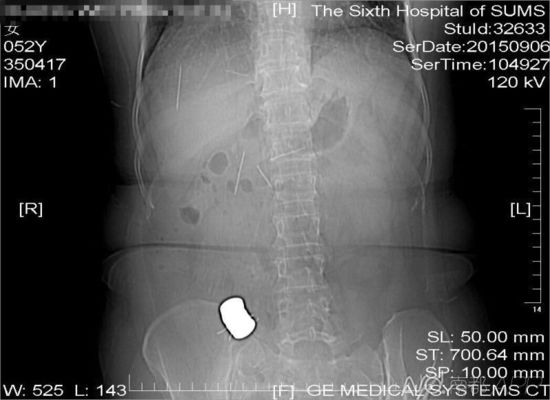

CT檢查結(jié)果中顯示,老人腹中有多個金屬異物和散落的繡花針

進行的CT檢查結(jié)果顯示,黃姨腹中有多個金屬異物和散落的繡花針。主管醫(yī)生黃俊博士介紹,這些針分別位于黃姨小腸內(nèi),部分已經(jīng)穿出小腸散播于腹腔內(nèi),還有部分金屬異物,最大的一塊上附著了數(shù)根斷針,有一根插進了胰腺,剩下的一根在脊柱附近,每枚約長4厘米。